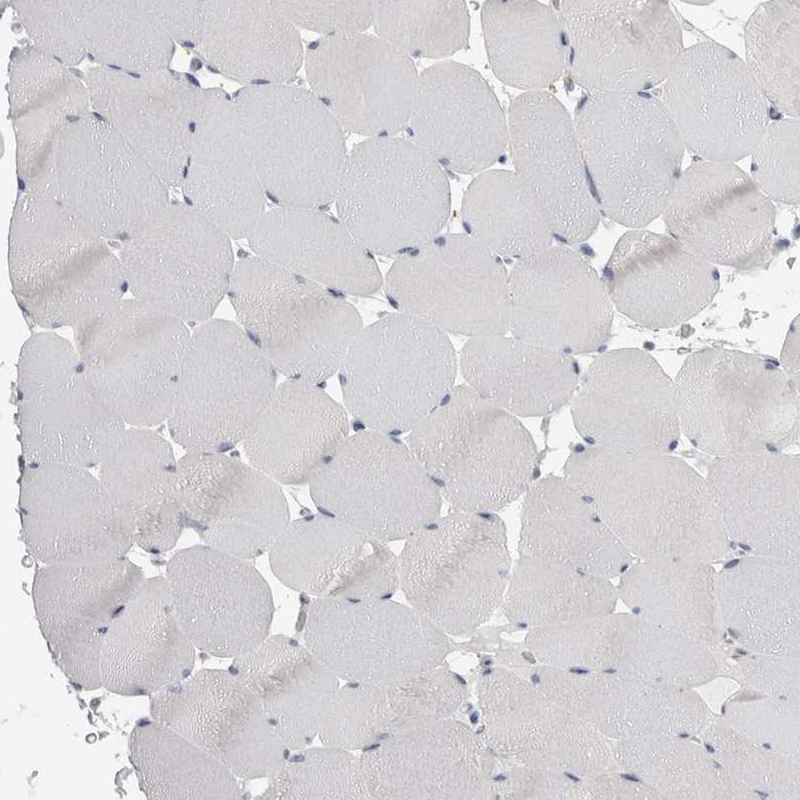

Immunohistochemistry analysis in human kidney and skeletal muscle tissues using HPA026077 antibody. Corresponding GATM RNA-seq data are presented for the same tissues.